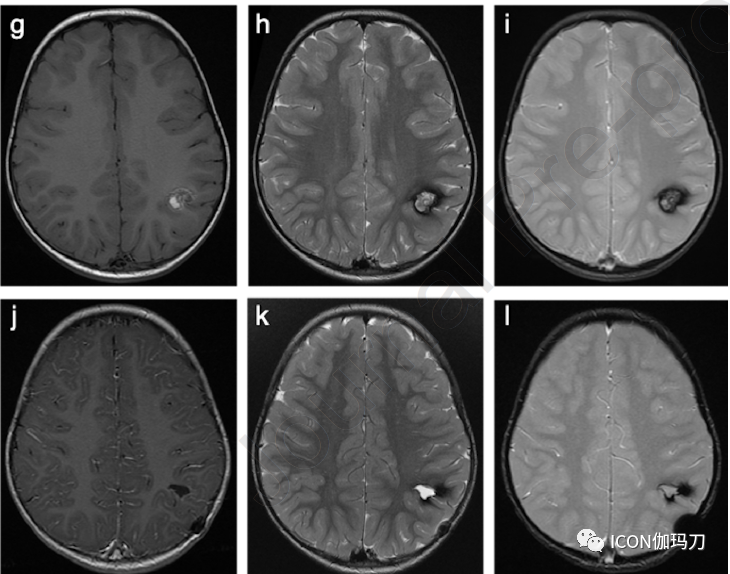

图3、所选轴位神经影像来自12岁男性,有左额CCM伴癫痫发作。(a)头部CT显示左侧额叶有偏心性钙化的高密度区域。(b) T2-WI和(c) T1-WI显示左额叶特征性小叶“爆米花”表现,信号强度不均,反映了血红蛋白破裂的不同阶段(高铁血红蛋白引起中央高信号,含铁血黄素沉积引起低信号边缘包围)。(d) SWI在同一位置显示显著的“开花”伪影,这是CCM的典型特征。靠近或累及大脑皮层的病灶可能是潜在的癫痫发作病灶(致癫痫灶)。对患者服用药物无法控制的癫痫灶进行显微外科切除,术后治愈。随访 MRI未发现残留病灶。

图4、所选MRI来自10岁女性,有2年偏身肌张力障碍病史。(a)轴位T2-WI显示右侧基底节区大的异质性病变,中央信号强度混合,符合巨大CCM。(b)轴位T2*-WI较好地显示周围低信号含铁血黄素边缘,并在右侧额叶胼胝体膝前部进一步发现小的点样CCM。(a)同期轴位T2-WI未发现相应的信号异常,进一步加强了SWI对CCM的诊断价值,特别是应积极寻找可能伴巨大CCMs的小的/微小的点样病灶。(c)冠状位T1-WI进一步显示巨大CCM的内部异质性和部分囊性。(d) (冠状位重建)Willis环飞行时间血管造影显示病灶没有动脉供血。进行DTI是考虑到巨大CCM位于高度重要功能区域:(e)斜冠状位和(f)轴向成角视图显示右侧皮质脊髓束及其与巨大CCM的关系。选择这些影像是为了更好地突出白质束及其围绕病灶的偏移,而不是显示病变本身。患者有家族性海绵状血管畸形(FCCM)家族史,KRIT1突变阳性(CCM1,常染色体显性遗传)。手术切除巨大CCM后,肌张力障碍明显改善。对较小的右侧额叶CCM进行SRS治疗,在随访影像中保持稳定。

图5、一名有学习困难和自闭症谱系障碍病史的14岁男性患者的T2-WI轴位(a)质子密度和(b)SRS治疗前定位MRI。在(b)中左侧丘脑CCM的典型表现(中心高T1信号,外周含铁血黄素环低信号)比(a)中显现得更好。注意周围基准标记。随访MRI是在5年后(a)和“难以抬起头部”临床状态恶化(b)时进行的。选择(c)轴位T2-WI ,与SRS治疗前成像相比(a)和(b) ,(d)冠状T2-WI和(e)矢状T1-WI显示在左侧丘脑CCM含铁血黄素沉积增加。3年后获得了进一步的磁共振(c-f)和SRS治疗后8年22岁(a - b) 时他的行为恶化。与(f)相比,(g)轴位T2-WI、(h)冠状T2-WI、(i)矢状T1-WI和(j)轴位SWI在与(c-f)相同的水平上显示稳定的表现,(g)没有进一步的开花现象。注意(e)和(i)中存在气管内插管。